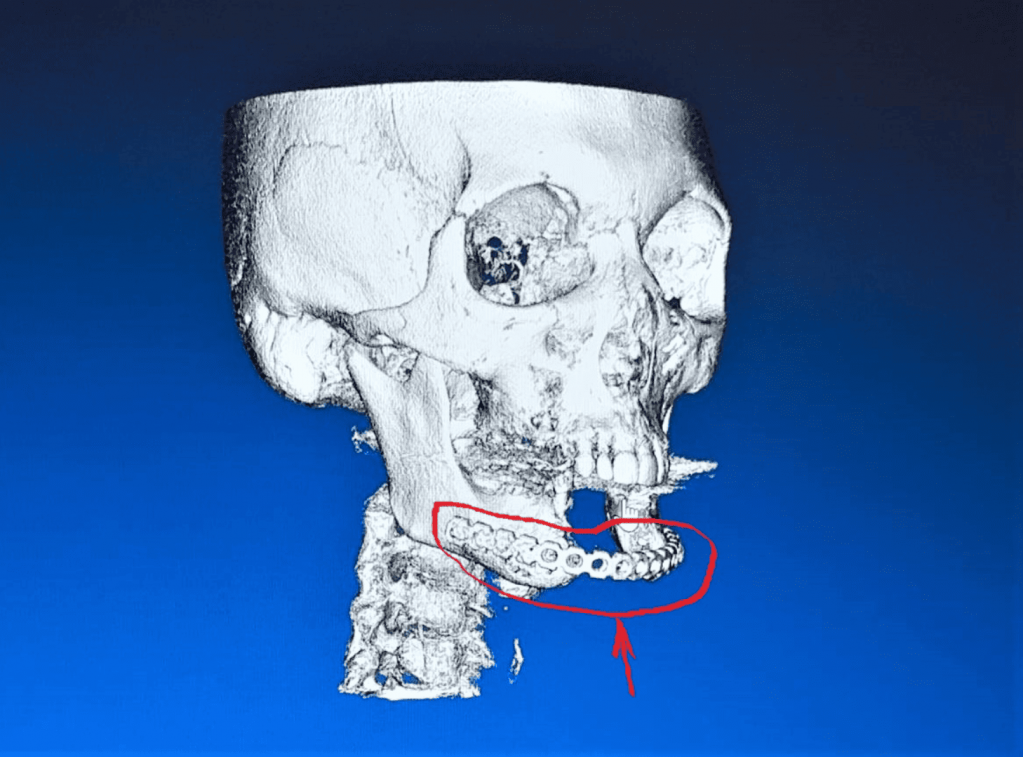

Хирурги предварительно создали 3Д-модель челюсти пациентки и по этим размерам сформировали трансплантат из малоберцовой кости.

По словам специалистов, сложность заключалась в том, что костный аутоимплантат был пересажен вместе с питающим кровеносным сосудом. Это было крайне важно для приживления и дальнейшей жизнеспособности пересаженной ткани.

При этом малоберцовая кость выбрана не случайно. Она имеет толстый слой, в который в последующем можно установить имплантаты для протезирования зубов.